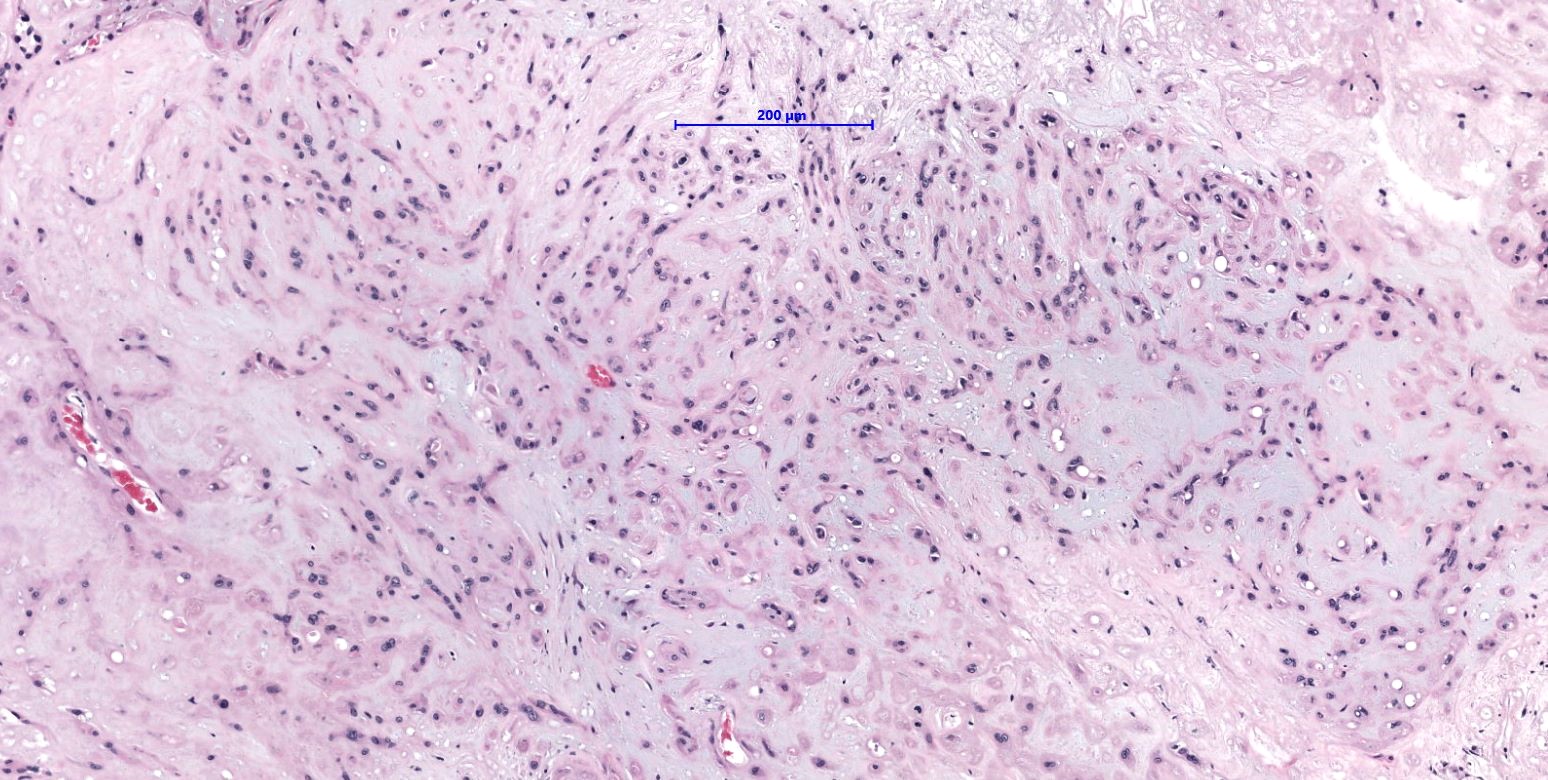

- WWTR1-CAMTA1 subtype (classic EHE):

- Cords, strands or small nests of large endothelial cells with abundant eosinophilic cytoplasm embedded in a myxohyaline stroma

- Tumor cells have vesicular, round to oval, sometimes indented nuclei

- Some tumor cells have intracytoplasmic, round, clear vacuoles representing small vascular lumina, which may contain erythrocytes

Microscopic (histologic) images

- Comment: Tumor is composed of cords and small nests of large endothelial cells with abundant eosinophilic cytoplasm embedded in a myxohyaline stroma. Immunohistochemically, the tumor cells are positive for ERG, CD31, CAMTA1, focally positive for keratin and are negative for CD34 and TFE3. The morphology and immunoprofile strongly support the diagnosis of WWTR1-CAMTA1 rearranged epithelioid hemangioendothelioma.